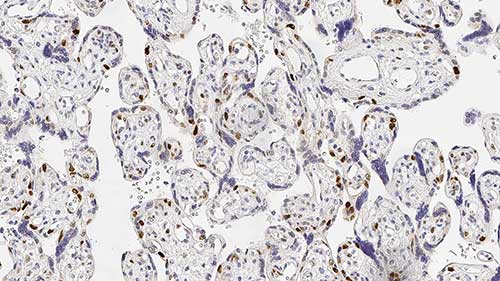

Human placenta: immunohistochemical staining for p57 protein. Note nuclear staining for cytotrophoblast and stromal cells of the villi. p57: clone 25B2

p57 est d'un intérêt croissant en tant que marqueur de maladies gestationnelles. Les maladies trophoblastiques gestationnelles comprennent un éventail de désordres de la prolifération du trophoblaste placentaire, présentant une large gamme d'apparences histologiques et de comportements cliniques.